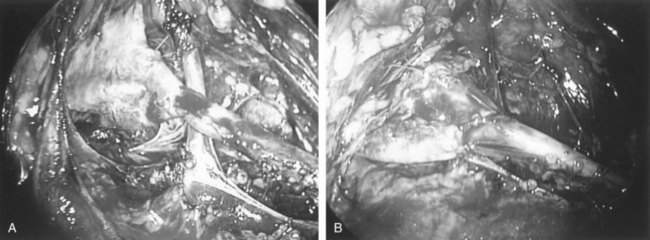

The initial transperitoneal approach to laparoscopic pyeloplasty was first described by Schuessler and colleagues (1993) and Kavoussi and colleagues (1993), and this approach has been the most widely used laparoscopic method due to its associated large working space and familiar anatomy. Before the laparoscopic portion of the procedure, cystoscopy with retrograde pyelography is first performed to define the anatomy and confirm the diagnosis, followed by placement of a ureteral stent and a urethral Foley catheter. The patient is placed in a 45-degree lateral decubitus position, and access to the peritoneal cavity is obtained via either the Veress needle or the Hassan access technique. Three to five laparoscopic ports are placed after the creation of CO2 pneumoperitoneum. Typically the umbilical port is for the laparoscope use. Colonic mobilization to expose the retropetioneal structures is the initial step of the laparoscopic procedure, although transmesenteric approach without bowel mobilization has been reported if renal pelvis or ureter can be readily recognized through the descending colonic mesentery (Romero et al, 2006). After medial mobilization of the colon, the ureter is identified and dissected in the cephalad direction to achieve mobilization of the ipsilateral proximal ureter, ureteropelvic junction, and renal pelvis (Fig. 41–13A). Extensive dissection of the ureter and excessive electrocautery use in close proximity to the ureter should be avoided to minimize injury to its vascular supply. At this time, the anatomy of the proximal ureter, renal pelvis, and nearby vasculature are carefully examined to determine the etiology of the ureteropelvic junction obstruction and the appropriate type of surgical repair. The general methods and principles of various types of surgical repair for laparoscopic pyeloplasty are identical to those described for open pyelplasty. If dismembered pyeloplasty is to be performed, which is suitable for the presence of crossing vessels, the renal pelvis is first transected circumferentially above the ureteropelvic junction and the lateral aspect of the proximal ureter is spatulated (Fig. 41–13B). The renal pelvis and proximal ureter are then transposed to the opposite side of the crossing vessel, if such vessel is present, and the ureteropelvic anastomosis is then completed with intracorporeal suturing techniques (Fig. 41–13C-D). In the presence of redundant renal pelvis, reduction pelvioplasty may be performed by excising redundant renal pelvic tissue and closing the pyelotomy. The actual laparoscopic suturing maneuver can be accomplished either freehand or with a semiautomated device (EndoStitch, US Surgical, Newark, CT). Either continuous running or simple interrupted suturing method may be used in the dismembered laparoscopic pyeloplasty, typically with the 4-0 absorbable suture. A surgical drain is placed after the completion of the anastomosis, and one of the trocar sites is typically used as the drain exit site.

Figure 41–13 A, Transperitoneoscopic view of a patient with left pyelplasty. The patient’s head is to the left. Note the proximal ureter is sandwiched between an anterior crossing lower pole renal artery (wrapped with white vessel loop and retracted upward) and a posterior crossing lower pole vessel (wrapped with white vessel loop). The suction-irrigator tip points at the left ureteropelvic junction. B, The left proximal ureter is being transected with laparoscopic scissors, revealing the preplaced ureteral stent within the ureteral lumen. C, The ureteral stent is transposed anterior to the anteriorly crossing vessel following circumferential transection of the proximal left ureter. D, Ureteropelvic anastomosis is completed with intracorporeal suturing techniques.

The initial retroperitoneoscopic approach to pyeloplasty was first reported by Janetschek and colleagues (1996). Cystoscopy with retrograde pyelography and ureteral stent placement are first performed as described earlier. For the retroperitoneal approach, the patient is usually positioned in the flank position with the use of flexion and elevation of the kidney rest. Following Hassan access technique to enter the retroperitoneum, a retroperitoneal working space can be created with balloon dilation. Following CO2 pneumoretroperitoneum, three to four laparoscopic ports are used to perform the laparoscopic pyeloplasty. The ureter is usually identified early in the procedure, and the dissection, mobilization, and ureteropelvic junction repair steps are identical to those described for the transperitoneal approach (Fig. 41–14).

Figure 41–14 A, Retroperitoneal laparoscopic photograph of a case with right ureteropelvic junction (UPJ) obstruction. Note the presence of a lower pole crossing renal vessel anterior to the UPJ. B, Intraoperative view of completed ureteropelvic anastomosis after retroperitoneal laparoscopic dismembered pyeloplasty.